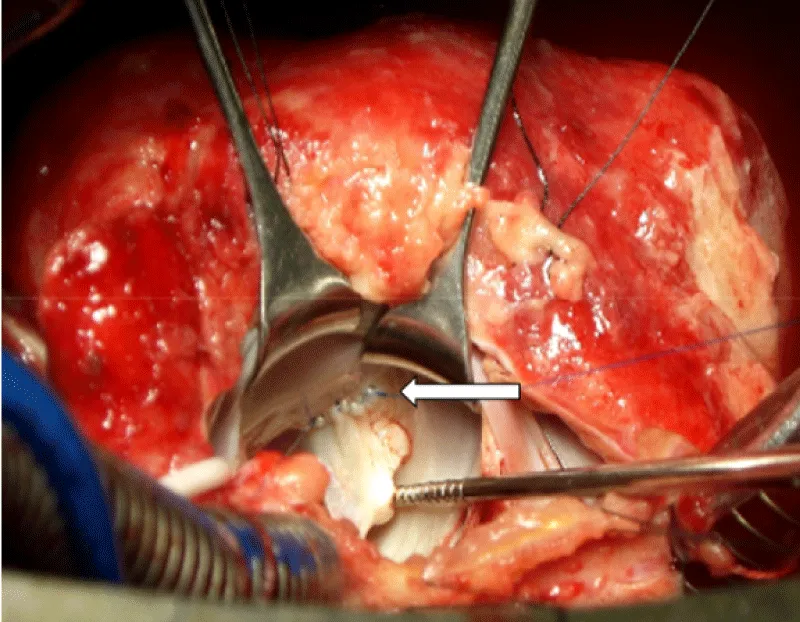

After sternotomy and opening of the pericardium which was thickened, an effusion with false membranes is revealed. There was no obvious bleeding point, and the point of break-in could not be objectified. After initiation of routine cardiopulmonary bypass, aortic cross-clamping and adequate myocardial protection, the mitral valve was exposed through a trans-septal approach, we revealed a 2 cm perforation in the anterior mitral valve (Figure 2). After suturing the defect (Figure 3), we proceeded to posterior mitral ring reduction by suture annuloplasty.

Figure 3: Continious suture of the tear of large mitral valve using 6-0 prolene (white arrow).

The subvalvular apparatus was undamaged.

The VSD was closed by two interrupted pledgeted prolene sutures (Figure 4).

Figure 4: Closure of the VSD (black arrow) by two interrurpted pledgeted prolene sutures (white arrow).